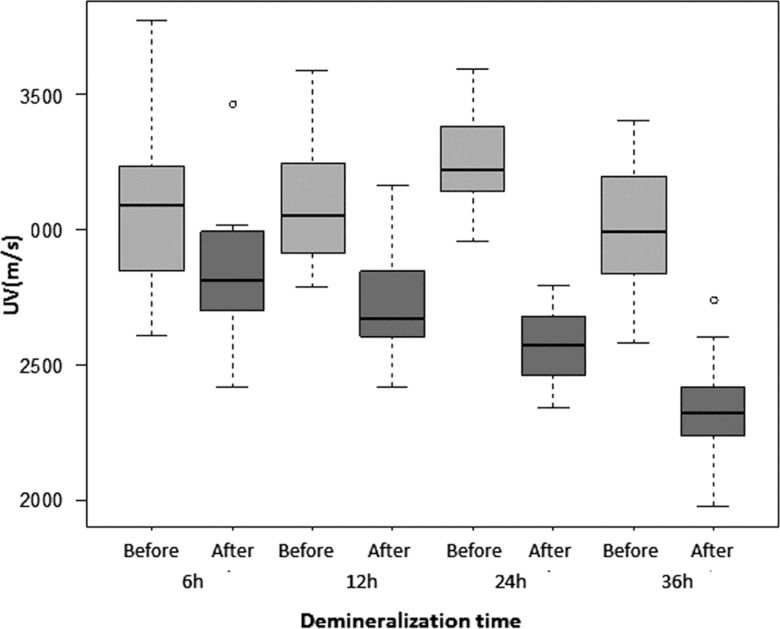

Ultrasound velocityThe pre-demineralization UV, as measured separately for each group (G6, G12, G24 and G36), ranged from an average of 2992 m/s to 3260 m/s, and the differences among groups were not significant. Post-demineralization UV progressively decreased with time from G6 (2840 m/s) to G36 (2327 m/s) to approximately 92.43% of the pre-demineralization value in G6, 87.39% in G12, 78.96% in G24 and 78% in G36. Significant differences (p<0.0001) were found between pre- and post-demineralization intra-group values for all groups (Table 1, Figure 5). The differences among the post-demineralization values showed variable significance for comparisons made between pairs of groups (G6xG12: p=0.0027; G6xG24: p<0.0001; G6xG36: p<0.0001; G12xG24: p=0.0037; G12xG36: p<0.0001; G24xG36: p<0.0001).

UV (m/s) data (mean±SD, range, median) before and after demineralization according to demineralization time (hours).

| UV | 6 h | 12 h | 24 h | 36 h |

|---|---|---|---|---|

| Pre- | 3078±303 | 3096±226 | 3261±184 | 2988±224 |

| (2611 - 3776) | (2789 - 3592) | (2958 - 3595) | (2579 - 3401) | |

| 3092 | 3055 | 3224 | 2992 | |

| Post- | 2840±238 | 2704±188 | 2573±130 | 2327±208 |

| 2419 - 3465 | 2419 - 3162 | 2341 - 2793 | 1975 - 2741 | |

| 2808 | 2674 | 2573 | 2319 |